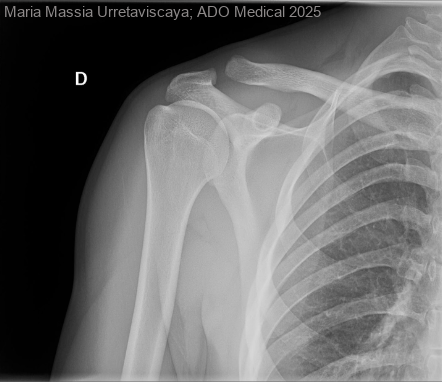

Osteólisis distal de clavícula secundaria a sobreuso deportivo: una causa infrecuente de dolor acromioclavicular en adulto joven

La osteólisis distal de la clavícula es una entidad poco frecuente que aparece principalmente en individuos sometidos a cargas repetitivas sobre la articulación acromioclavicular (AC), especialmente deportistas que realizan levantamiento de pesas, natación o actividades...